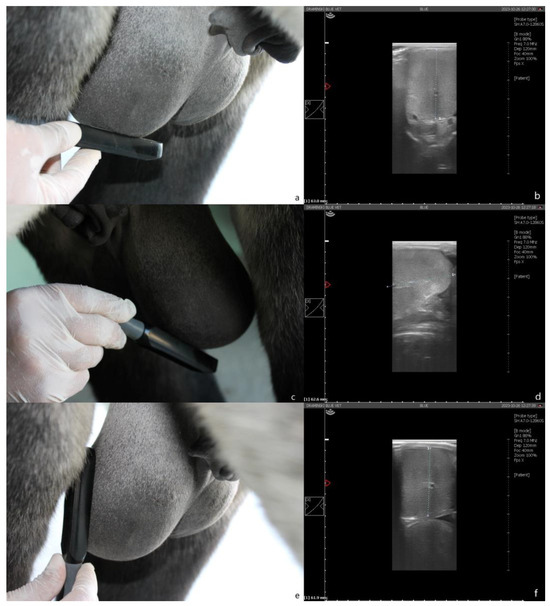

2.3. Testicular Measurements and Volume Calculation